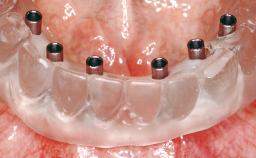

Immediate Loading of Eight Implants in the Maxilla and Six Implants in the Mandible and Final Restoration with Three-Unit and Four-Unit FDPs

Extensive scientific evidence has confirmed that immediately loaded implants with fixed full-arch provisional restorations can osseointegrate with success rates similar to conventionally or delayed loaded implants. A number of immediate-provisionalization techniques for edentulous jaws have been described. Some protocols differ when it comes to prefabricated provisional templates versus complete denture conversion; intrasurgical impressions versus direct relining; and cemented versus screw-retained provisional restorations. In this context, complete-denture conversion has been proposed for either intrasurgical impressions or direct relining. Another possibility is the utilization of a prefabricated provisional to be adapted either in the mouth (by direct relining) or in the laboratory (on a working model obtained from an intrasurgical impression).

# of Implants 14

Type of Implants One-Piece

Modality 6+ implants with immediate loading

Loading Protocol Immediate